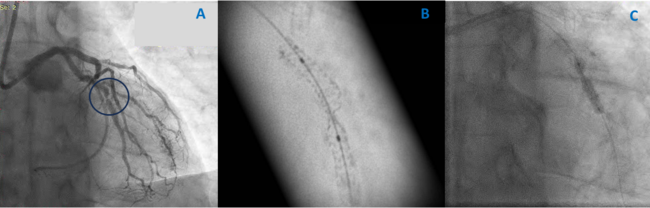

Coronary angiography showed a severely underexpanded stent in the OM1, confirmed by stent boost and caused by calcification (Figure 1A and B). Advancement of intravascular ultrasound (IVUS) through the stenosis was not feasible. Dilatations with noncompliant balloons failed to expand the previously implanted stent (Figure 1C). It was decided to proceed with ELCA (Philips). Although lasing with a 0.9-mm catheter under saline injection failed, subsequent lasing under contrast injection achieved lesion ablation (Figure 2A, Video 1, Video 2). A noncompliant balloon was then dilated symmetrically, allowing adequate stent expansion illustrated by stent boost and IVUS (Figure 2B-E).